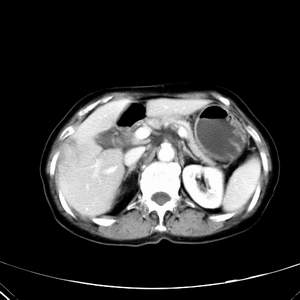

患者,女性,77岁,右上腹胀痛月余。afp正常。ca125升高。即往无肝炎病史。

肝右叶病灶是胆管细胞癌吗?门静脉右支癌栓形成?右侧肾上腺有问题吗?

最后5幅图片是延时7分钟的。门静脉右前支内有充缺吗?如有,肝血管瘤不好解释。

渐进性强化,中间见沙砾样钙化,首先考虑血管瘤

病灶渐进性向心性强化,延时病灶中心见条片状高密度影,局部见肝包膜回缩征,结合病人无肝炎病史,考虑肝右叶胆管细胞癌,门脉右支癌栓形成。